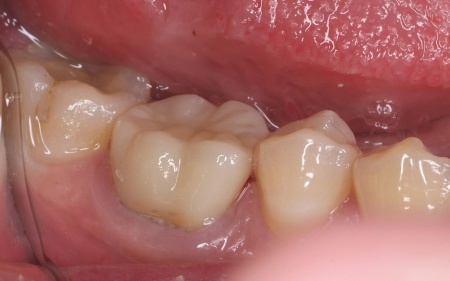

| 行ったご提案・治療内容 | 欠けた被せ物は10年以上前に治療した部位とのことで、材質はセラミックの一種であるポーセレンだと考えられます。 再び破折する危険性を考慮して、セラミックの中でも人工ダイヤモンドと呼ばれるほど高い強度をもつ「ジルコニア」での修復を提案し、同意いただきました。 メリット デメリット まずは右下奥歯の古い被せ物を除去し、歯の形を丁寧に整えます。 後日、完成した被せ物を装着し、見た目や噛み合わせに問題がないことを確認して、治療を終了しています。 |

治療後